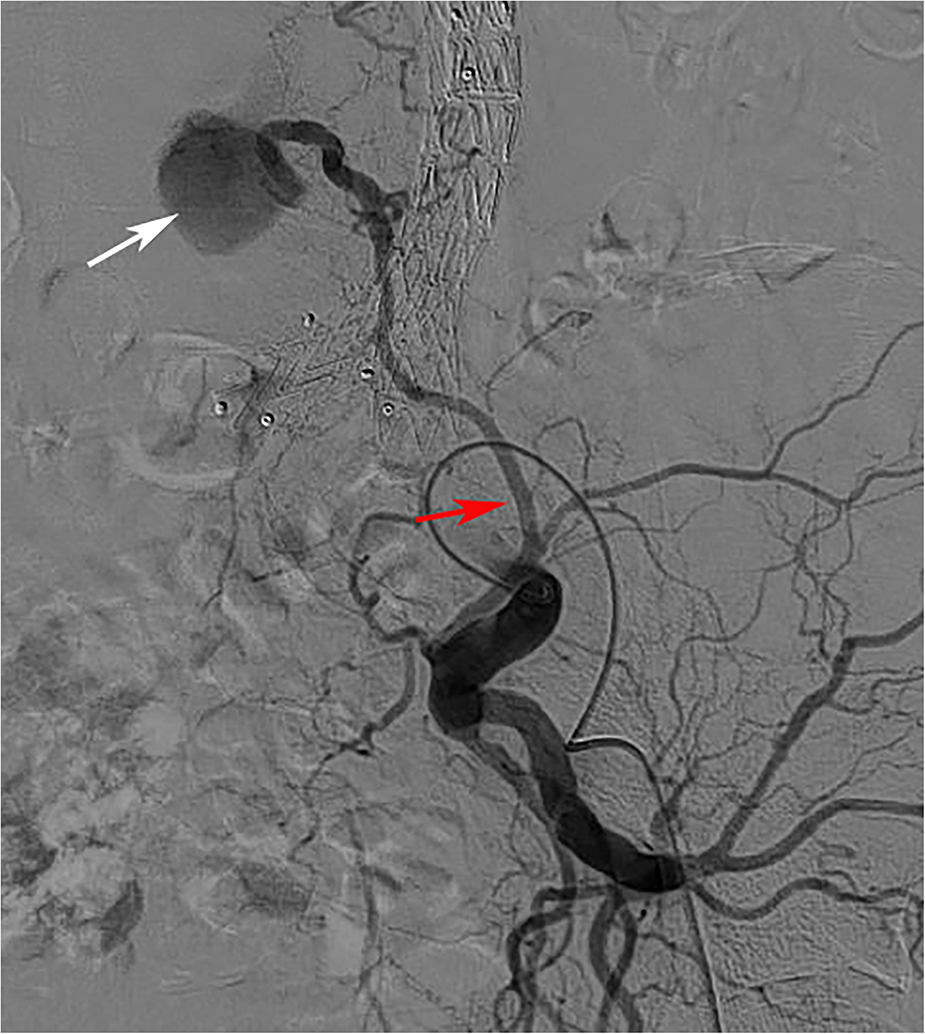

In addition, the relationship between ILA and T2ELs has not been compared, although it has sometimes been found to be the source of T2ELs during follow-up (Figure 5). In our study, the right ILA diameter measured based on abdominal CTA was 2.31 ± 0.65 mm, and the left ILA was 2.30 ± 0.66 mm, which was similar to previous results based on human anatomy, which reported that the diameter was 2.7 ± 0.6 mm (39). We found that 28.0% of ILAs originated from the posterior of the IIA, 69.9% from the main trunk of the IIA, and 0.2% from the CIA. Kiray et al. (40) reported an average ILA diameter of 3.7 ± 0.7 mm, and Teli et al. (25) reported an average ILA diameter of 3.5 ± 0.5 mm. Koc et al. (23) reported that the ILA diameter originating from the main trunk of the IIA was smaller than that originating from the posterior branch of the IIA. In addition, the iliac lumbar artery mainly originates from the main internal iliac artery and less from the posterior branch of the IIA and CIA (25, 39, 40). This finding was similar to our study.

Figure 5

The iliolumbar artery was a source of type 2 endoleak. (Red arrow is the ILA, white arrow is the aneurysm cavity).

In the T2ELs caused by ILA, we found that ILA tended to be backward and upward, but only 2% of T2ELs were caused by ILA. There was no significant difference in the anatomical characteristics of the ILA in univariate analysis, and the right ILA diameter also showed no difference in multivariate analysis (p = 0.83). T2ELs from the IIA reported in the past are relatively rare, and the incidence of most previous report series is between 0% and 3.8% (21, 41), and no correlation was demonstrated in previous studies (22, 42). Other risk factors associated with T2ELs include chronic kidney disease, advanced age, aneurysm sac volume, and aneurysm sac thrombus volume (34, 43–46). Although our study did not find a statistical correlation between ILA and T2ELs, T2ELs caused by ILA still deserve attention.